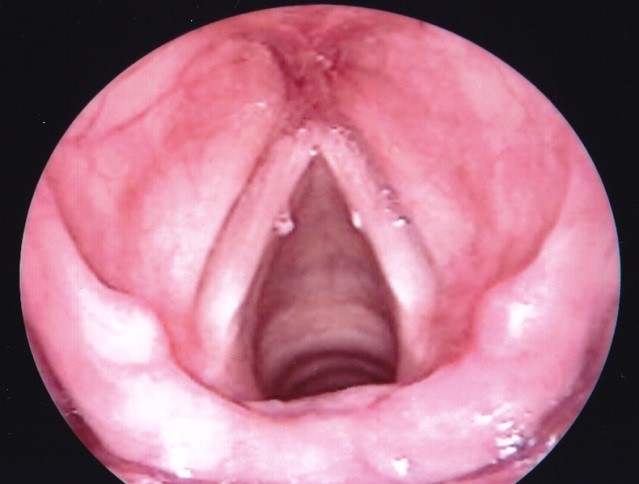

Hạt xơ dây thanh thường xảy ra hai bên ở 1/3 giữa dây thanh. Nguyên nhân chính của chúng là lạm dụng giọng nói mãn tính – la hét, la lớn, hát to, hoặc sử dụng một tần số thấp không tự nhiên.

Chẩn đoán dựa trên hình ảnh trực tiếp hoặc gián tiếp của thanh quản bằng gương hoặc ống nội soi thanh quản. Sinh thiết tổn thương nghi ngờ để loại trừ ung thư được thực hiện dưới VI PHẪU THANH QUẢN.